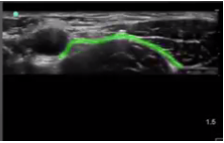

Femoral Fascia Iliaca Highlighted Image

Highlighted Area: Fascia Iliaca